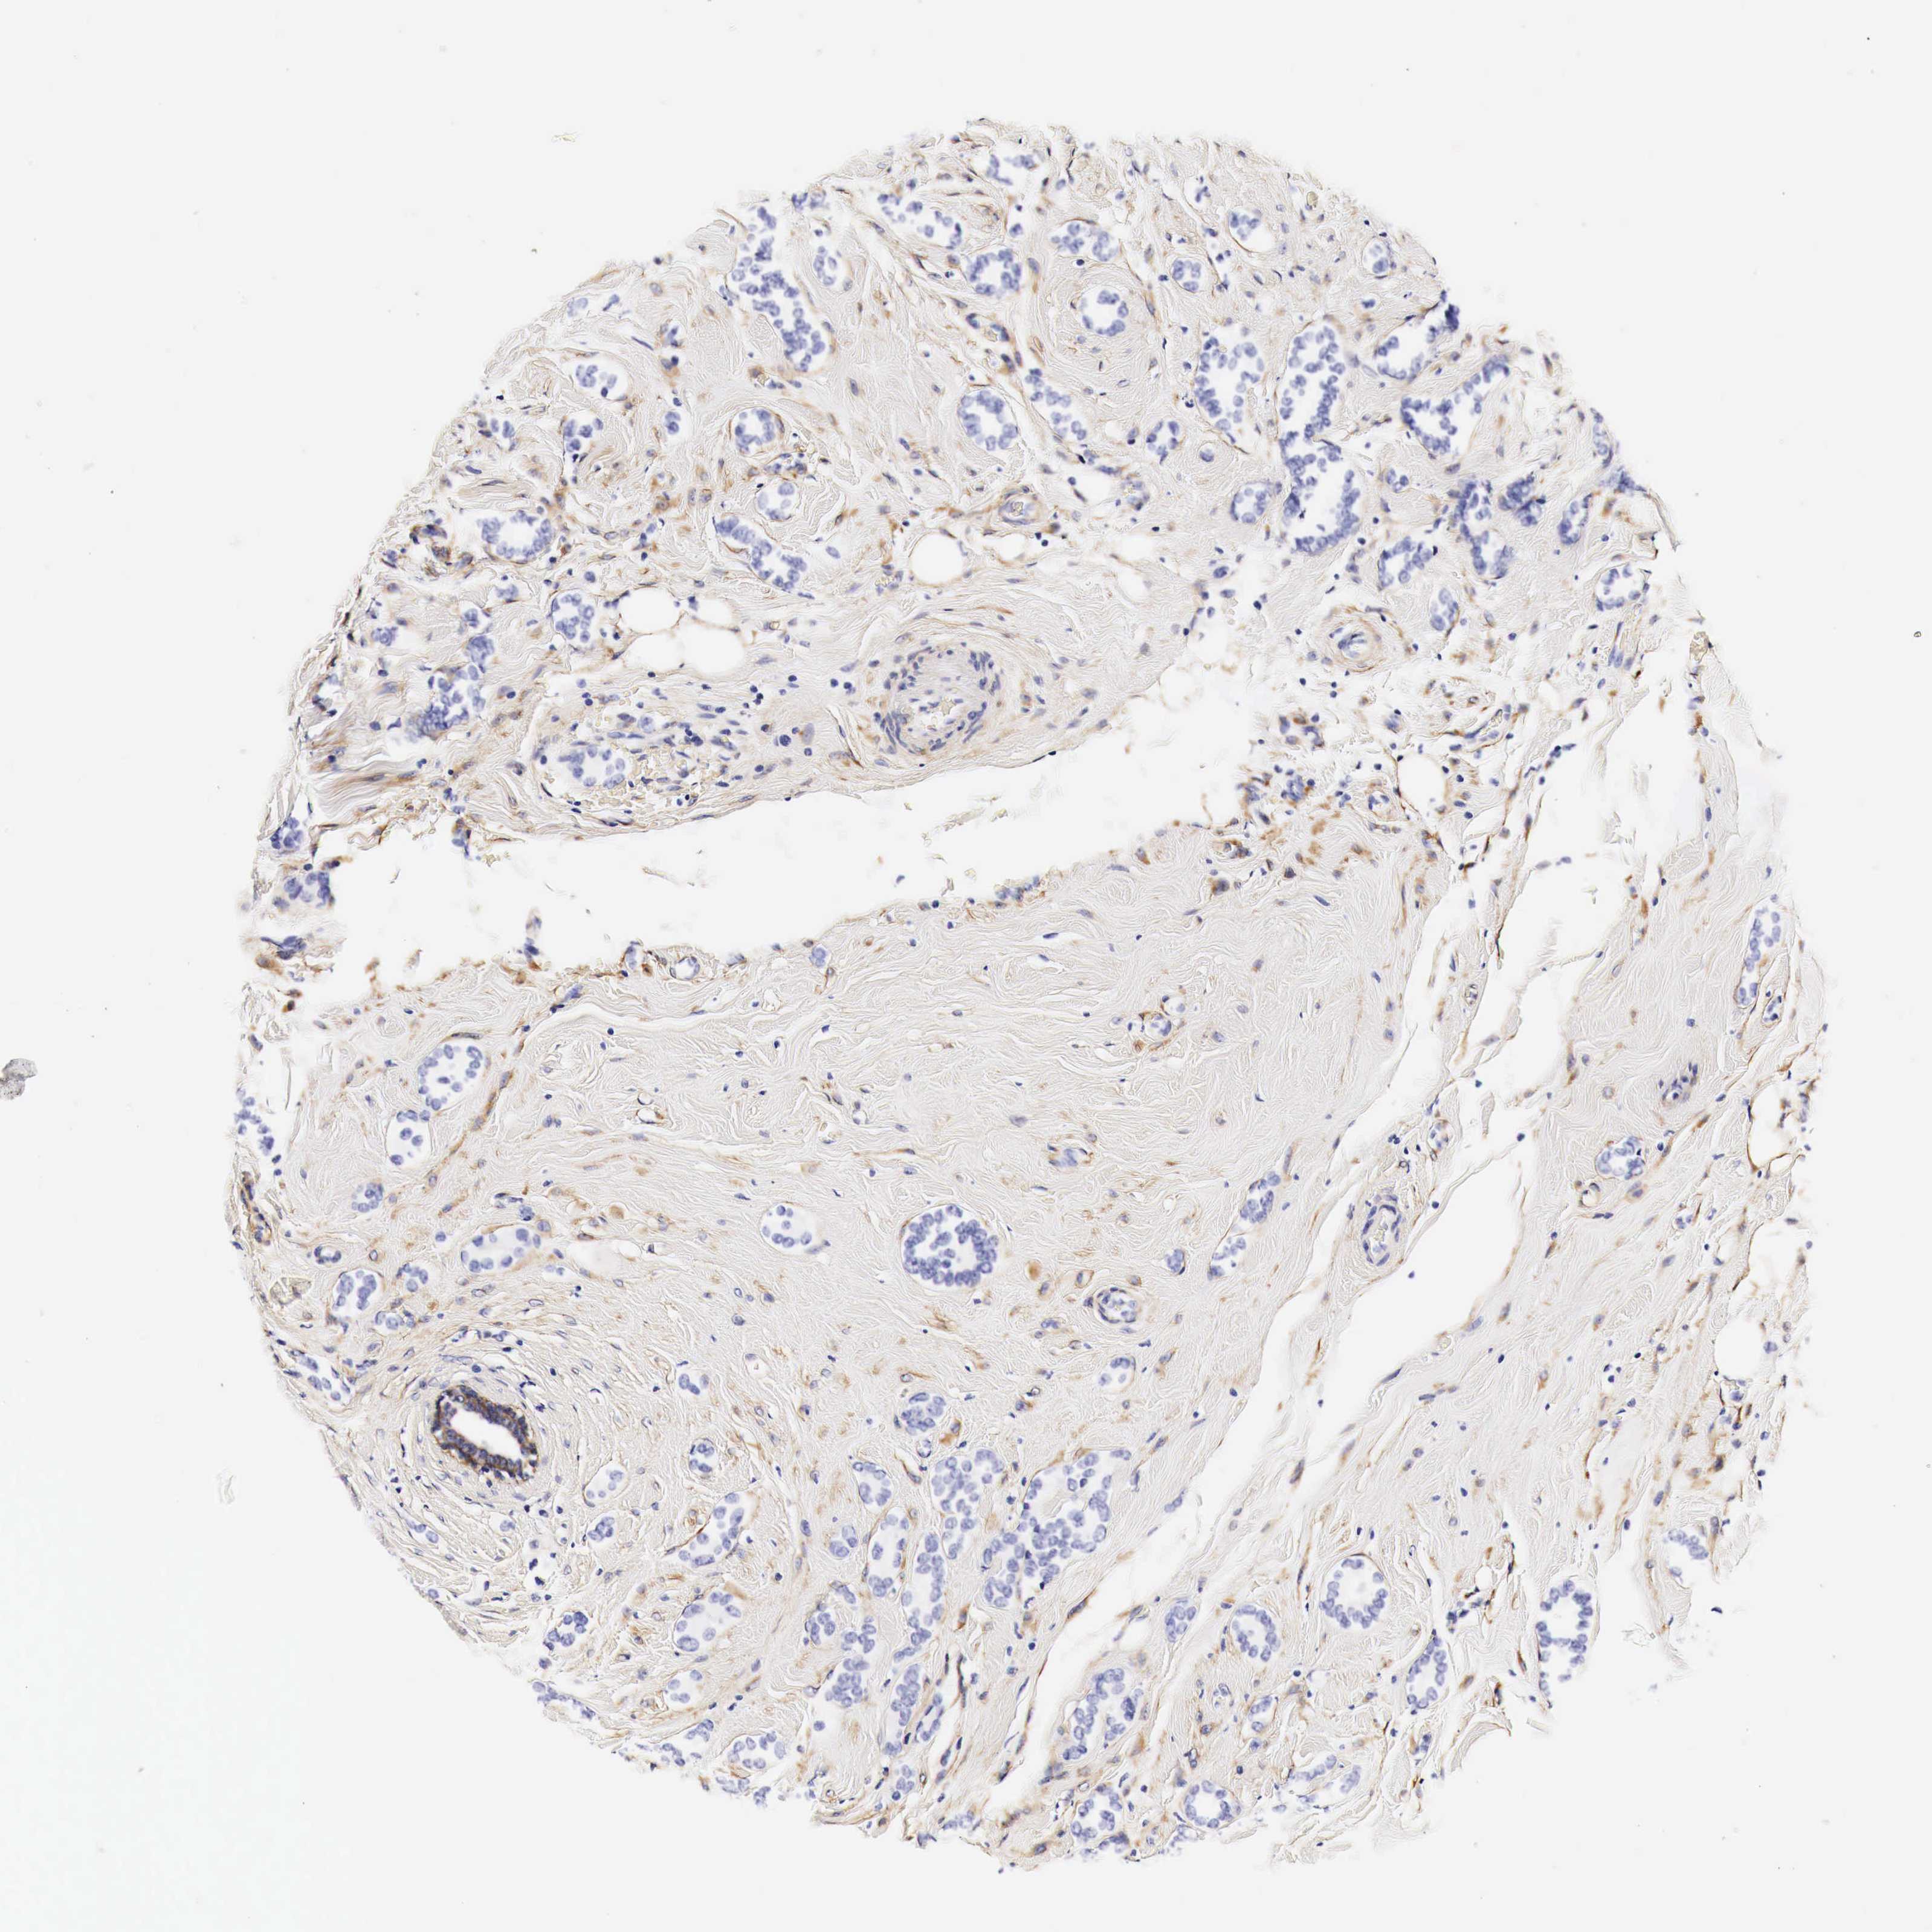

CANCER BREAST CANCER Show tissue menu

BRCA TCGA BRCA VALIDATION PROTEIN EXPRESSION

ANTIBODIES

AND

VALIDATION